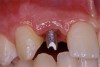

Before the day of surgery, the patient was seen by the orthodontist for the removal of the orthodontic brackets. The patient still was not pleased with the position of the two centrals, and it was determined that this would be addressed after implant placement (Figure 13A). The anatomical variations of the crestal tissue and lack of interdental papilla can be appreciated in the close-up views of the right and left sites (Figure 13B and 13C). There were no surprises on the day of surgery as all of the decisions were made during the planning phase, before the scalpel ever touched the patient. The occlusal view of the CT 3D model revealed the wider alveolar ridge on the right side and thinner crest on the left side (Figure 14A). This was confirmed when the full thickness mucoperiosteal flaps were elevated, and the underyling bone revealed (Figure 14B). The tooth-borne templates were designed to facilitate the drills and drilling sequence specific to the diameters of the predetermined implants (Figure 15A). Each template contained an embedded 5-mm long stainless steel tube, which was approximately 0.2-mm wider than each drill (just wide enough to allow for the drills to rotate freely). Once positioned over the natural teeth, the template was secure and offered precision accuracy in transferring the implant locations from the original software-designed plan, allowing the potential for internal and external irrigation (Figure 15B). The 3.7-mm diameter Tapered Screw-Vent implant drilling sequence requires three drills: pilot, intermediate, and final sizing. Thus, three separate templates were fabricated to a.commodate these sizes. The templates were removed easily and replaced with the next sequential size in less time than it takes to change the drill on the surgical handpiece. After the osteotomies had been.completed, the implants were delivered to the site (Figure 16A and Figure 16B). For this internal hex connection implant, the author r.commends that the flat of the antirotational hex be positioned to the facial for proper orientation of the restorative.components (Figure 17A). Preprepared margins were created from a milled titanium fixture mount transfer post, which was delivered to the implant as support for an immediate transitional restoration. The facial “dot” helped confirm the orientation of the abutment to the facially positioned flat side of the internal hex connection (Figure 17B). Before cementation of the transitional acrylic restorations, a closed-tray, fixture-level impression was made, and a soft-tissue model fabricated.

Figure 16a  After (A) the osteotomies were completed, (B) the implants were placed.

Figure 16a

Figure 16b  After (A) the osteotomies were completed, (B) the implants were placed.

Figure 16b